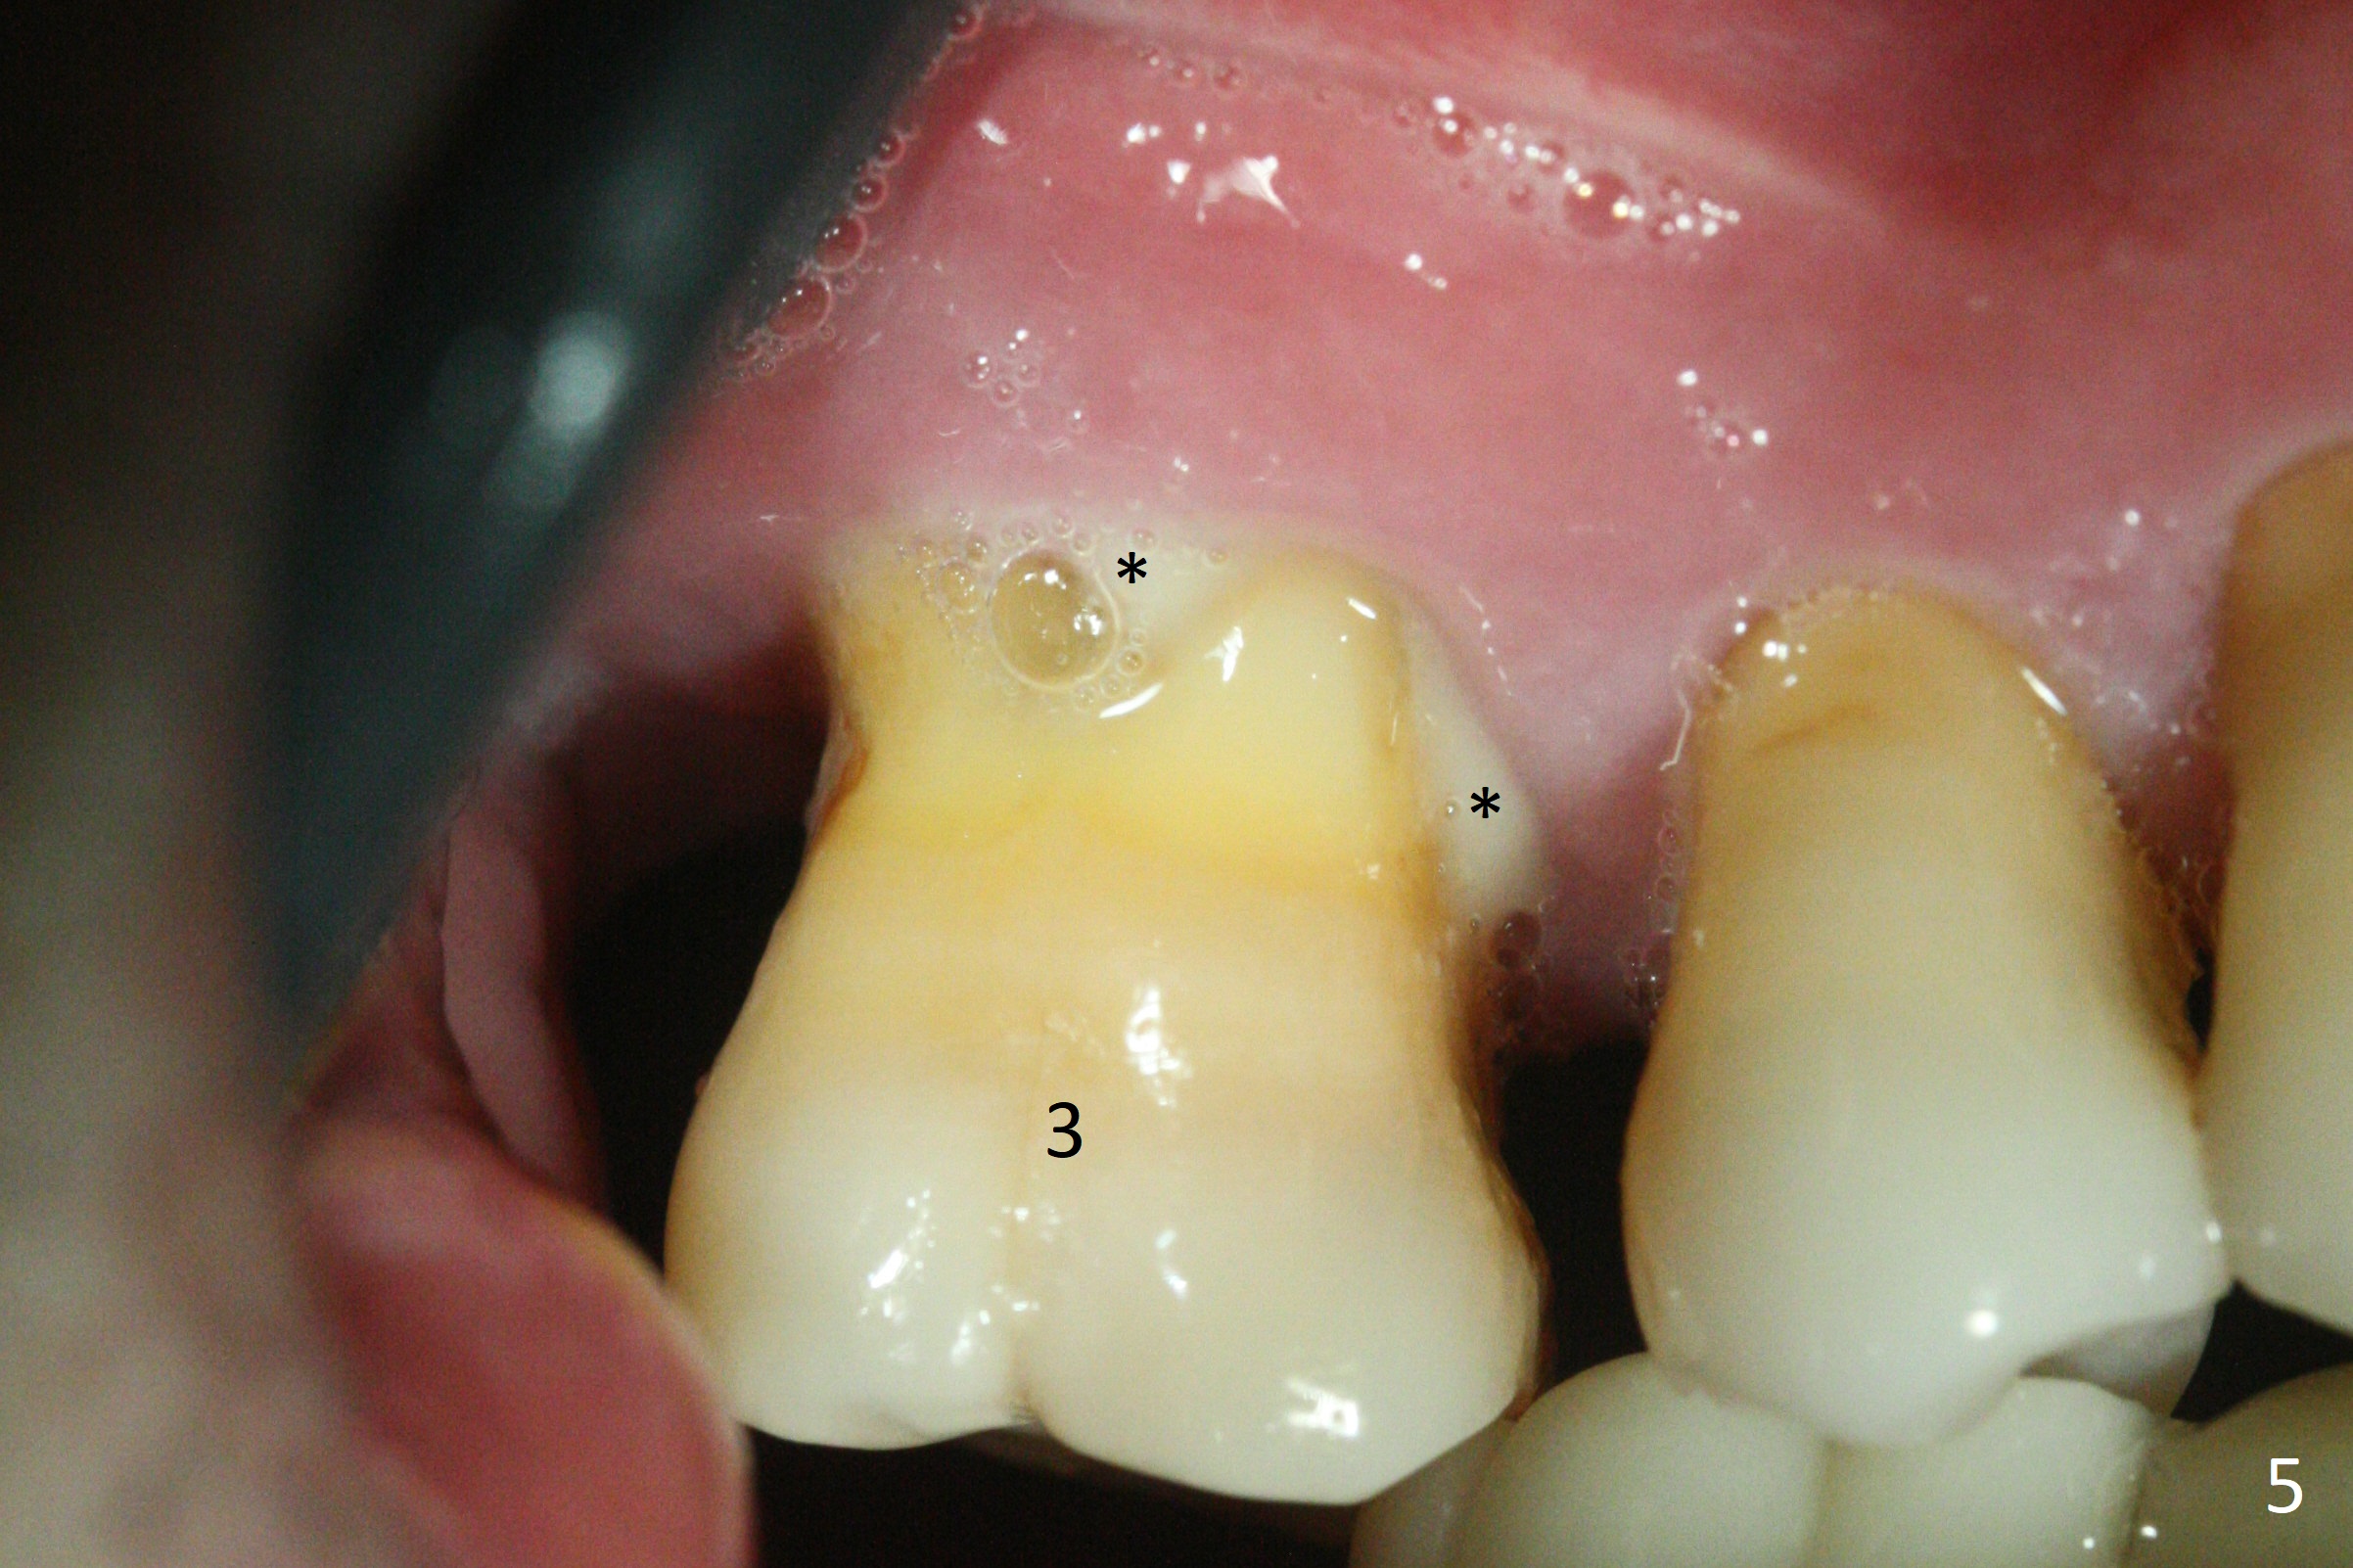

A 44-year-old man requests an implant at #3 because of mobility. It appears that the bone height decreases from 6 mm (Fig.1,2: 3 years ago) to 4 mm (Fig.3,4, recently). After extraction and Clindamycin treatment, take PVS impression of the socket. Use initial drill with drill stopper of 3 mm and round burs with stoppers from 4 to 5 mm. If the buccal (B) and palatal (P) plate defect is severe, use a regular implant. Otherwise use an extra wide one. The advantage of the latter is length as short as 6 mm vs. 8 mm for the regular one. For the latter, 2 mm of the implant will be in the sinus (Fig.4 red box), 4 mm in bone (pink box) and 2 mm in the socket (orange box; to be surrounded by bone graft). Since the gingiva is 6 mm (Fig.4 green box), an abutment with 6 mm cuff should be chosen. To reduce occlusal interference, select abutment height 4 mm.

Recently periodontal abscess occurs with purulent discharge from the buccal sulcus (Fig.5 *) and palatal gingiva erythema and edema (Fig.6 *). The buccal and palatal plates are most likely defective. A small diameter implant should be placed. The infection at #3 may be the cause of failure of implant at #31 (redo).